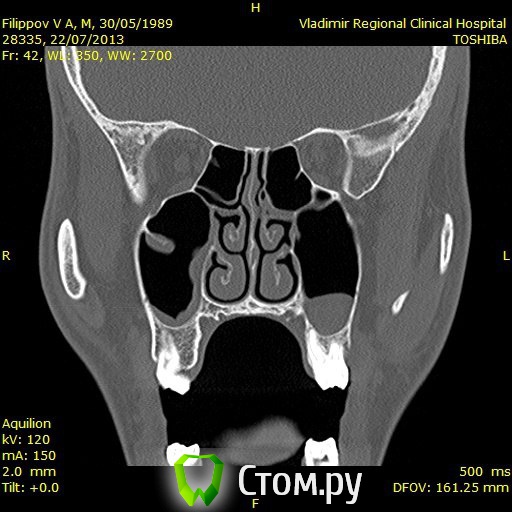

Доброго времени суток,помогите пожалуйстабеспокоит заложенность носа уже 3ий год,обший ослабленный иммунитет что выражается в частых простудах,возраст 25 лет,причина этого гдето в зубах,так как кроме этого проблем небыло никогда,когда начились эти проблему начал ходить к стомалогам мне сделали порядка 7 пломб,в одном был пульпит,как пульпит переличили стало легче но не до конца ,затем на мскт увидели кисту под депульпированной 7кой,

вот зуб пролечил у ильи мера,в 2 этапа,первый раз он сделал,и залили лекарство и сказал зуб врядли сохраним,через месяц второй прием все доделал и сказал что все хорошо,после этого общее состояние стало хуже,возможно из-за того что врач сказал что все с пульпы сливалось прямо в пазуху, вот это делали в марте ,после этого сделал мскт киста с зуба увеличилась с 1см до 1,5см, я лег в больничку местную и мнее ее вырезали,после этого прошел 1 месяц улучшений нет все также заложенность в носе и пониженный иммунитет,не подскажите что делать?кисту просто вырезали резекцую корня зуба не делали вот снимки до вырезания кисты после первого раза лечения каналов